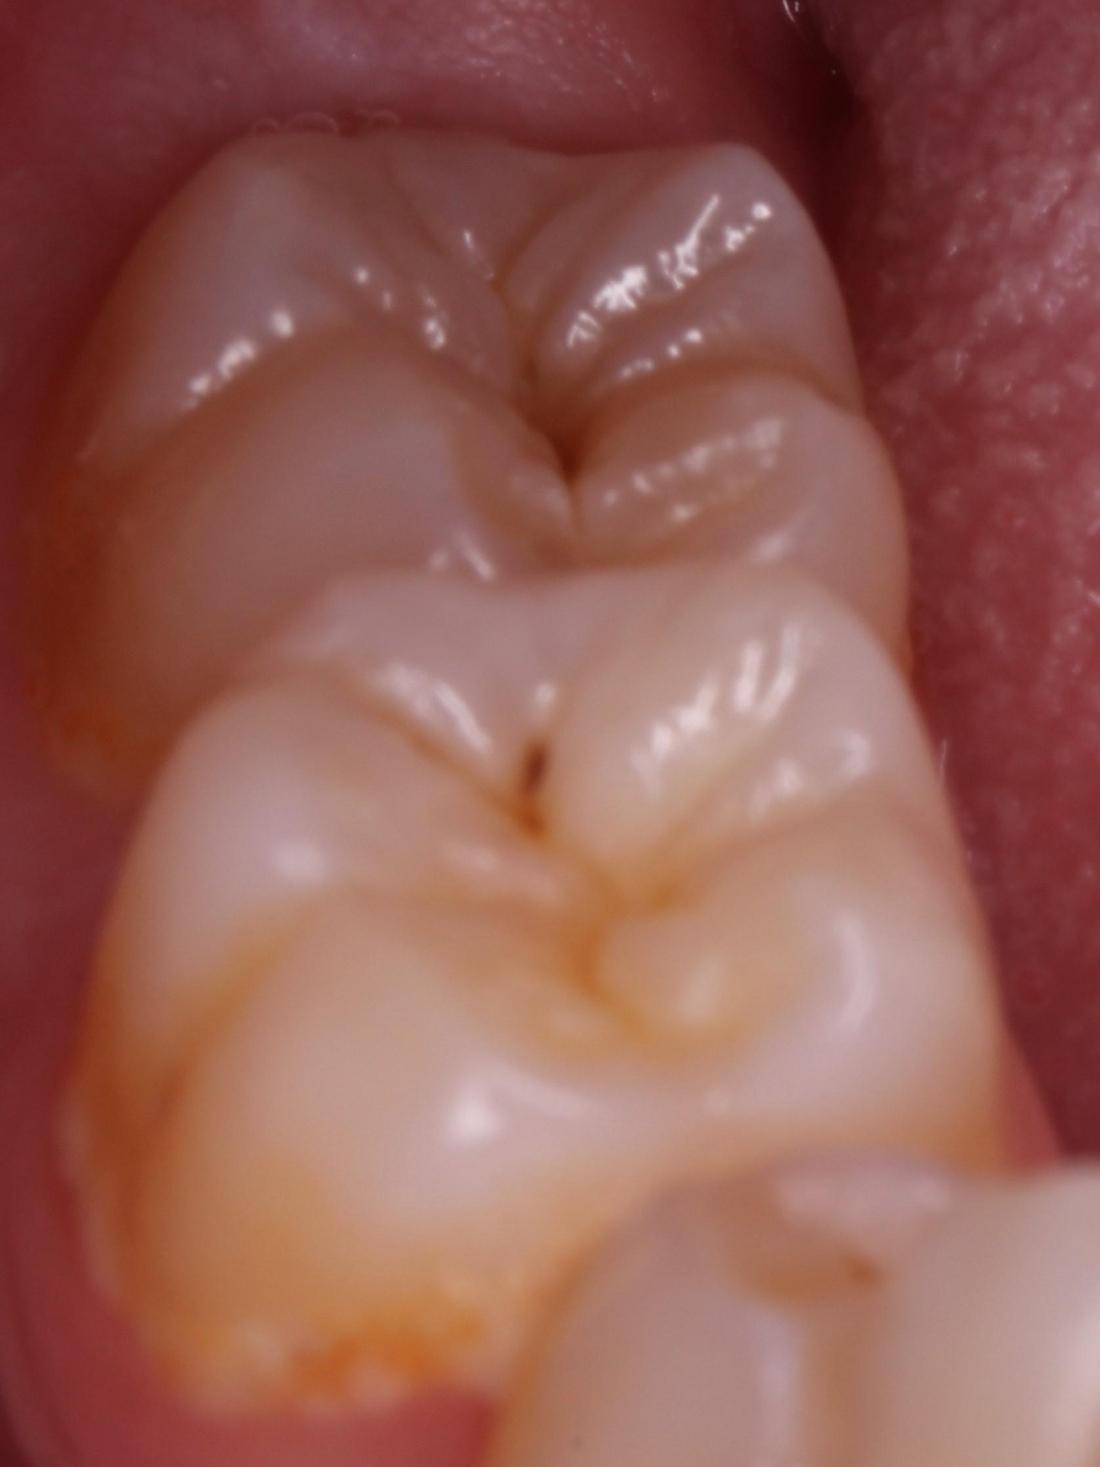

Posterior Filling

A common location children develop cavities are in their posterior (back) teeth on both the biting surfaces and in between the teeth.  When using composite material to complete these fillings, Dr. Molly is able to remove less tooth structure because the material will bond to the tooth when placed.  This will help increase the longevity of the tooth which is especially important when completing fillings on children and adolescents.